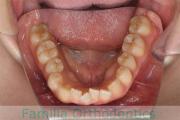

No.22V-299

- 上顎前突

- 叢生

- 30歳

- 女性

- 上:

- 44

- 下:

- 主な使用装置:

- FEA 022

- 治療にかかった費用:

- 90万円

上の出っ歯、口が閉じにくい、下の前歯のガタガタを治したいということで来院されました。上顎から左右小臼歯を、下の前歯は凹凸が非常に強いので、こちらから一本抜歯を行いました。2年強、30回程度の通院が必要でした。

成人になってからの叢生(でこぼこ、凹凸、ガタガタ)は、保定をしっかりしないと後戻りをしてしまうリスクが高いです。